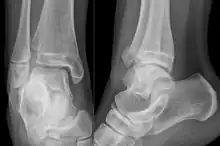

| X-ray of a Tillaux fracture in an 11 year old female | |

A Tillaux fracture is a Salter–Harris type III fracture through the anterolateral aspect of the distal tibial epiphysis.[1] It occurs in older adolescents between the ages of 12 and 15 when the medial epiphysis had closed but before the lateral side has done so,[2] due to an avulsion of the anterior inferior tibiofibular ligament, at the opposite end to a Wagstaffe-Le Fort avulsion fracture